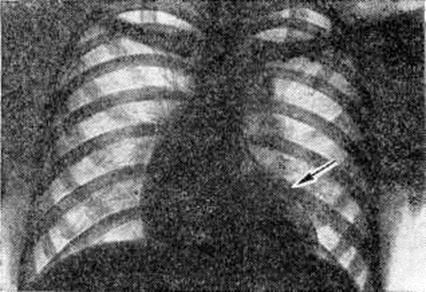

Рентгенограмма грудной клетки больного с дефектом межжелудочковой перегородки (прямая проекция): тень сердца увеличена за счёт обоих желудочков, заметное выбухание дуги лёгочного ствола (указано стрелкой), лёгочный рисунок в прикорневых отделах лёгких усилен.

При рентгенологическое исследовании у больных со средними и большими дефектами перегородки находят увеличение обоих желудочков, усиление лёгочного рисунка в прикорневых отделах лёгких и расширение тени лёгочных сосудов (рисунок 10). С развитием лёгочной гипертензии размеры сердца несколько сокращаются, начинает выбухать дуга лёгочного ствола, ослабляется периферический лёгочный рисунок, резко гипертрофирован и увеличен правый желудочек.